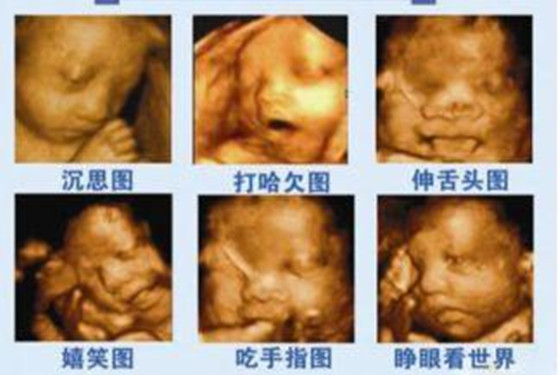

怀孕五个月时胎儿已经长出了头发,眉毛和指甲了,此时胎儿的头部如鸡蛋般大小,他们身上的皮肤也显得不那么透明了,胎儿宝宝在麻麻肚子里可以自由的活动,一些比较调皮的胎儿会毫不留情的在麻麻肚子里“闹腾”,从四维彩超图片可以观察出胎儿的具体动态,他们偶尔会吸吮自己的手指玩耍,好似困了还会打打哈欠,饿了也会做出吞咽动作,有的时候会对麻麻的肚皮“拳打脚踢”,有时也会揉揉自己的眼睛,还有的时候胎儿也会玩弄脐带等等,总之胎儿宝宝在麻麻肚子里面不会那么“乖巧听话”,他们也有自己的一套作息时间,饿了会吃,泛了会睡,无聊时也会玩耍戏弄。